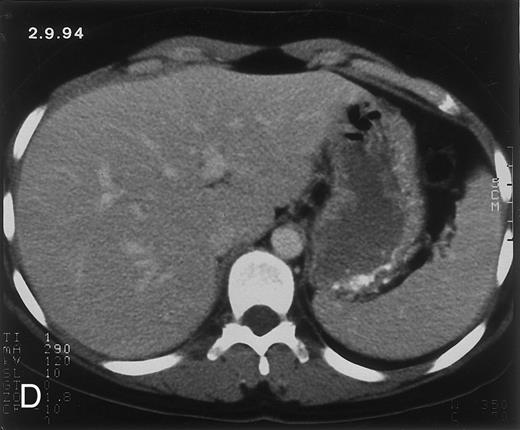

Radiologic evolution in patient A. (A) Postcontrast abdominal CT scan on March 16, 1993 shows multiple small hypodense areas in all segments of the liver, suggestive of hepatic candidiasis. Seven days previously, the patient had recovered from severe neutropenia after the first cycle of chemotherapy for AML. (B) On April 23, 6 days after the neutrophil count had dropped below 500/μL in the second cycle of chemotherapy, there is no evidence of focal lesions on postcontrast CT scan. (C) On June 18, when neutrophils were normalized for 46 days, CT scan again shows multiple small abscesses.

(D) On August 23, 15 days after the neutrophil count had dropped below 500/μL in the third chemotherapy cycle, focal liver lesions clearly decreased in size and number. (E) On September 30, 35 days after neutrophil recovery, multiple hepatic abscesses are seen (arrowhead). To show maximal extent of lesions the scan shown is at a slightly different level. (F) On June 16, 1994, 230 days after neutrophil recovery, the CT scan has normalized.